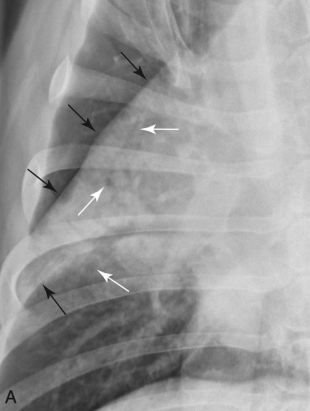

Tram line

Doughnuts

๊ธฐ๊ด€์ง€๋ฒฝ ๋‘๊บผ์›Œ์งˆ ๋•Œ ๋ณด์ด๋Š” sign

ํ ๋ง๋‹จ์œผ๋กœ ๊ฐˆ์ˆ˜๋ก ๊นจ๋—ํ•œ ๊ฒŒ ์ •์ƒ

๋ง๋‹จ์—๋„ tram line ๋ณด์ด๋ฉด ๋น„์ •์ƒ

VS.

(์™ผ์ชฝ์ด ์ •์ƒ, ๋ง๋‹จ์œผ๋กœ ๊ฐˆ์ˆ˜๋ก ๊นจ๋—. ๋ง๋‹จ์—๋„ tram line ๋ณด์ด๋Š” ์˜ค๋ฅธ์ชฝ์€ ๋น„์ •์ƒ.)

ํฐ์ƒ‰: doughnuts, ๊ฒ€์€์ƒ‰: trams)